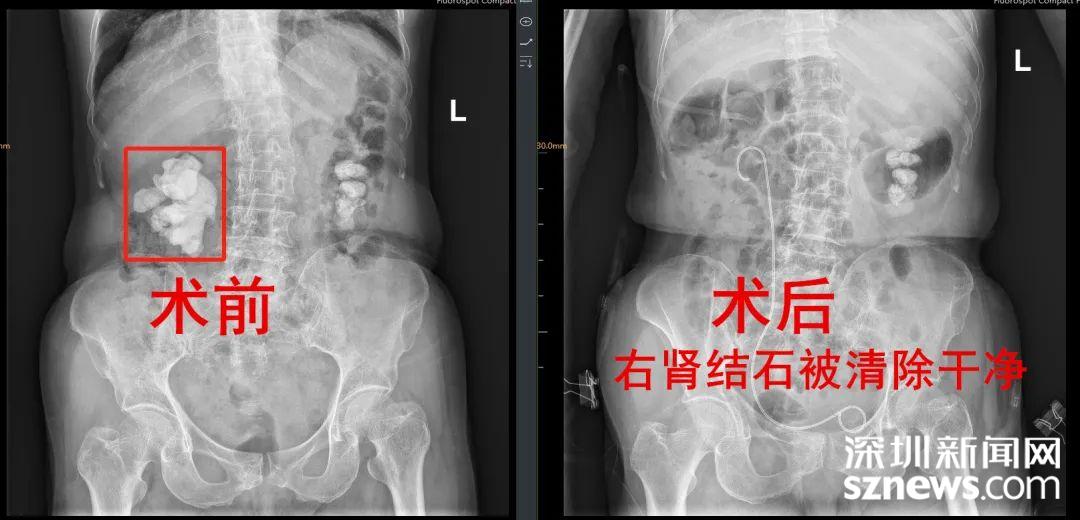

“看到这片阴影了吗,这都是肾结石!”CT检查结果出来后,接诊医生王晓彬指着片子向李奶奶解释道,“右肾这个结石大小约75毫米×60毫米×40毫米,这是最难治的完全鹿角形肾结石,得尽快手术。”

专家在李奶奶腰部肾的体表投影处开一个约0.5厘米的小孔,通过小孔建立一条从皮肤到肾脏的通道,再通过这个通道把肾镜置入肾盂,利用激光、超声等碎石设备,把肾结石击碎取出。

这样,术中仅仅利用一个通道就把李奶奶右肾的大结石全部清除掉了。

术中出血极少,术后李奶奶肾造瘘管引流袋颜色清亮,复查KUB未见明显结石残留。